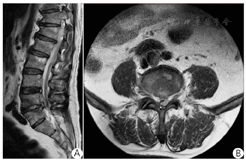

典型病例:57岁男性,顽固性腰痛1年、加重伴左下肢放射痛1个月。家中养羊、长期羊群接触史。体查示:L4~5棘突压痛、叩击痛;直腿抬高试验左侧阳性约40°、加强试验阳性约30°;左小腿前外侧、足背皮肤感觉减退。临床诊断为LBS,给予药物抗布鲁菌病、止痛及营养神经等保守治疗,腰痛症状无明显改善、且出现进行性左下肢麻木。行UBE下减压、清创、椎间融合联合经皮螺钉内固定术。术前、术中及术后影像学资料见图1,图2,图3。

注:A为术前MRI T2WI示:L4~5椎管层面硬膜外脓肿呈高信号;B为术前MRI横断面示:硬膜外脓肿压迫硬脊膜和神经根